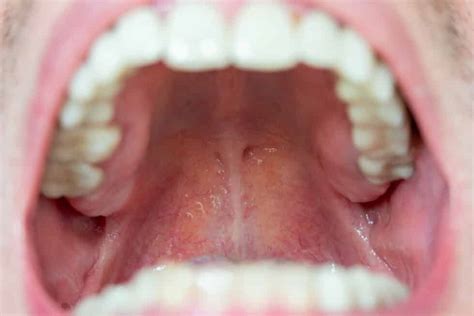

Para detectar posibles síntomas es importante conocer cómo luce un paladar sano. Este tiene un aspecto rosado y presenta un color uniforme, lo que implica que uno de los primeros signos de alerta sea un cambio en su tonalidad, pasando a un tono amarillento, un rojo más vivo o incluso, un tono blanquecino. Otro posible síntoma puede ser la aparición de llagas, sensación de boca seca, escozor en el propio y malestar generalizado en la boca.

Paladar inflamado.